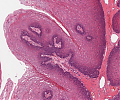

A60 Plattenepithelpapillom

Papillär aufgefaltetes Plattenepithel mit Akanthose.